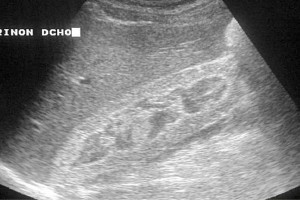

Diplomados en Ultrasonografía